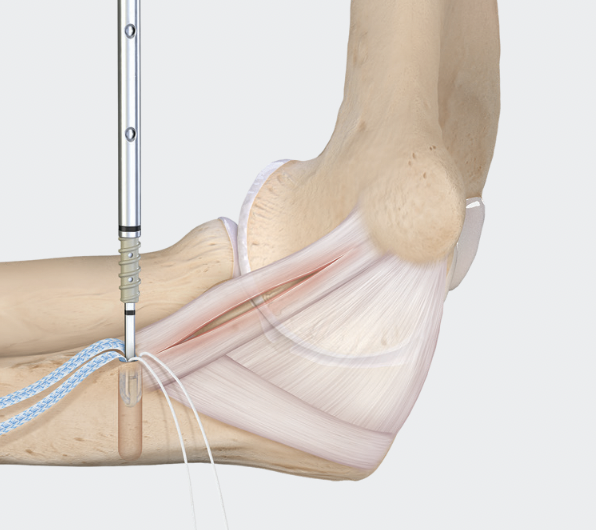

Technique

Medial incision over medial epicondyle

- protect ulna nerve

- split FCU

- expose ulna collateral ligament

- repair avulsion from medial epicondyle / sublime tubercle as indicated with anchor

- ensure isometric